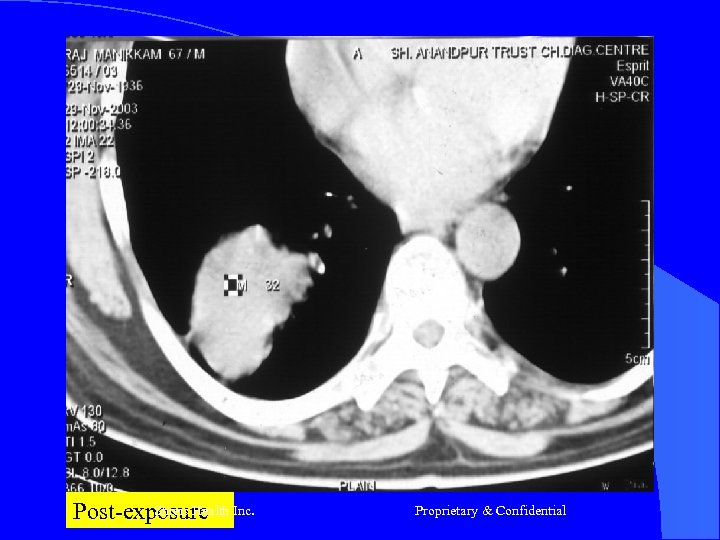

Case- 1 l l l Mr R, 68 yrs Nov-2003 -Ca Lung RLL T 2 N 0 (Adeno ca) Chemo – (Carbo + Eto) 3 # till March 2004 April 2004 – Prog of disease (vide CT) Presented – Cough Hemoptysis - Breathlessness - Pallor - Debility Shreis Health Inc. Proprietary & Confidential

Case 1 RFQMR-1#26/11/2004 – 09/12/2004 2# 24/12/2004 – 07/1/2005 l CT – Jan 2005 – Aug 2005 - Static l Now No Complaints - Energetic - Walks 30 m daily Appetite Good l Shreis Health Inc. Proprietary & Confidential

Shreis Health Inc. Pre-exposure Proprietary & Confidential

Shreis Health Post-exposure Inc. Proprietary & Confidential

Post-exposure Inc. Shreis Health Proprietary & Confidential